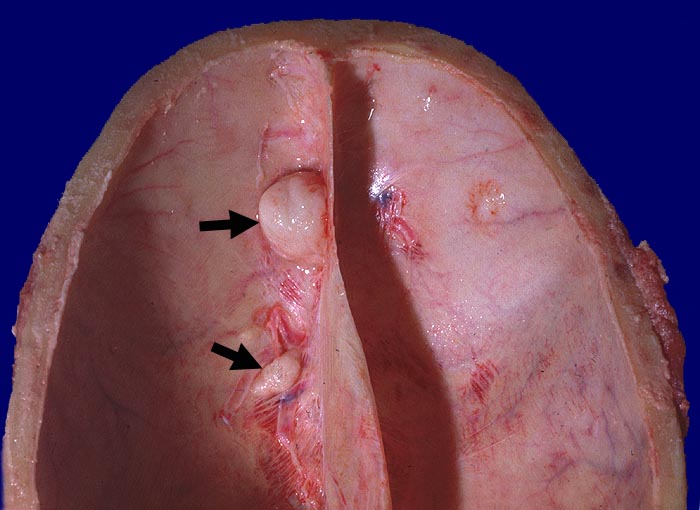

Die meisten Meningeome sind gutartig und fallen in die Kategorie WHO Grad I. Atypische Meningeome (WHO Grad II) machen zwischen 4.7-7.2% aller Fälle aus, anaplastische Menigeome (WHO Grad III) sind noch seltener. Meningeome sind oft multipel bei Patienten mit hereditärer Prädisposition und bei Neurofibromatose 2 sowie bei 10% der sporadischen Fälle. Meist wachsen Meningeome langsam. Sie sind in der Regel scharf begrenzt und sitzen der Dura breitbasig auf. Das Einwachsen von Meningeomgewebe in die Dura mater und/oder die benachbarte Schädelkalotte ist noch kein Malignitätszeichen und noch durchaus vereinbar mit einem benignen Meningeom WHO Grad I. Demgegenüber ist das Einwachsen in das benachbarte Hirnparenchym in aller Regel atypischen oder anaplastischen Meningeomen vorbehalten. Die Konsistenz ist prall-elastisch oder fest und das Tumorgewebe kann fokal verkalkt sein. Das Meningeom en plaque bedeckt flächenhaft die Dura als dünne Platte.

• Der Dura breitbasig aufsitzender scharf begrenzter halbkugeliger Tumor.